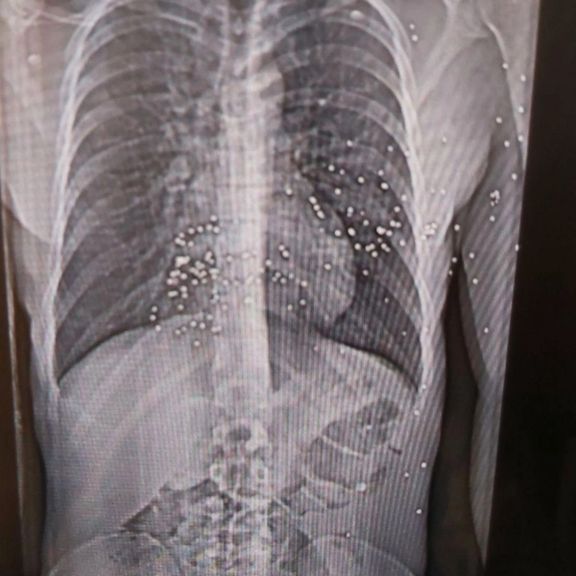

نیویورکر نوشت اعضای کادر درمان در هفتههای اخیر خود به مستندسازی شواهد حملات حکومت به مردم ایران پرداختهاند و برخی مدارک از جمله تصاویر سیتیاسکن مجروحان را در اختیار این مجله قرار دادهاند.